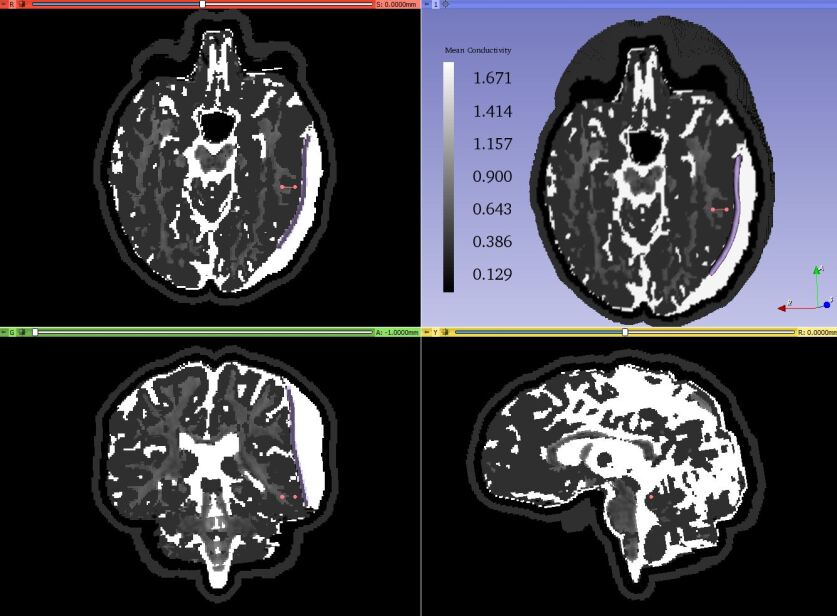

Refer to caption

Figure 4: Tissue label maps based on deformed by insertion of electrodes postoperative image data (predicted postoperative MRI) within 3D Slicer (axial, sagittal, coronal and 3D view). Tissue classes are colored as follows: scalp (pink); skull (yellow); GM (gray); WM (white); and CSF (blue). The location of the electrode grid array can be identified by the line of black voxels in the vicinity of the right temporal and parietal lobes.

Figure 7: Mean conductivity of the deformed model based on image data deformed by implantation of electrodes shown in axial, sagittal and coronal view overlaid with deformed MRI and 3D brain model in 3D window within 3D Slicer. The current dipole moment vector is denoted by the pink line with two fiducial points. The electrode sheet is denoted by the purple color.

We demonstrate the application of our framework by solving an iEEG forward problem. We solved the iEEG forward problem with a current dipole source using the deformed image data with the actual electrode locations. We put a dipole in the gray matter of the brain with a dipole moment of 100 µAmm to replicate a current dipole set up by cortical neurons. Fig. 7 shows mean conductivity of the deformed model based on image data deformed by implantation of electrodes. Fig. 8 shows the predicted distribution of electric potential within the brain computed using the model based on the deformed image data with the actual electrode positions. We used deformed image data with actual electrode positions to avoid the error introduced by using incorrect tissue geometry. As discussed in our previous study [23], the correct geometry can reduce the effect of inaccuracy of source localization.